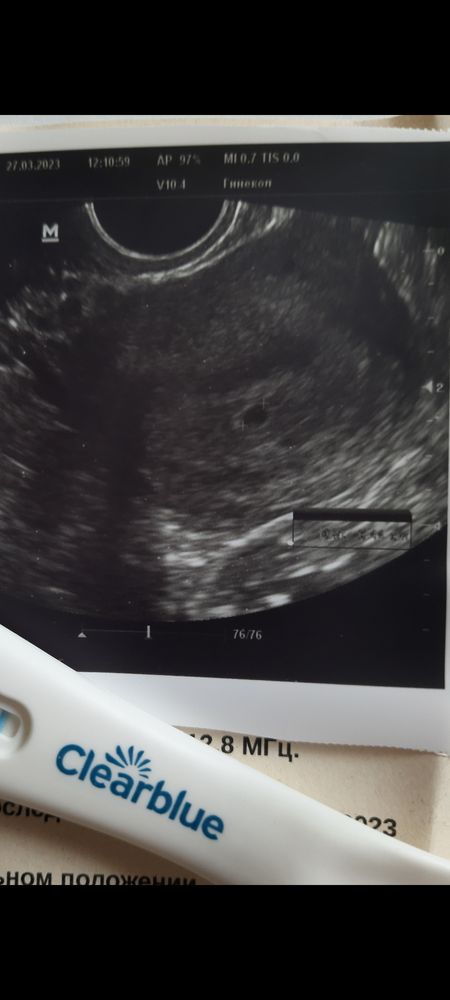

Изображение Изображение27.04 было около 4х недель от даты зачатия И 24.04 это уже перед постановкой на учёт Ходила проверяла что бы не было внематочной Ну и фотка нужна была для сюрприза)